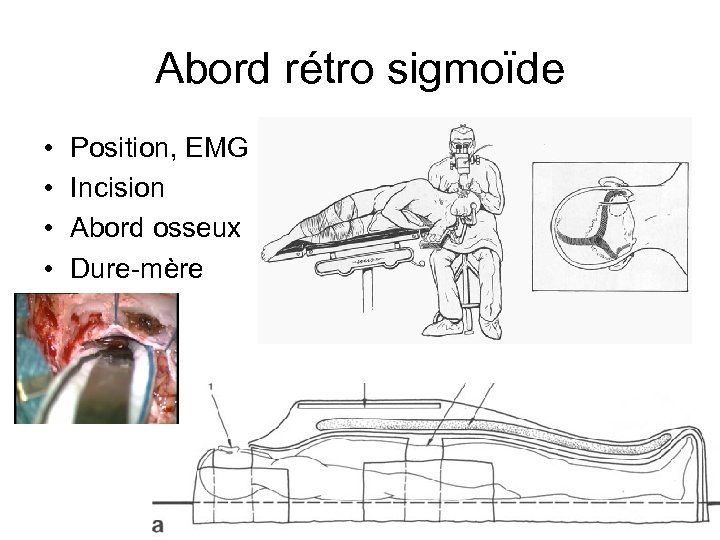

Abord rétro sigmoïde • • Position, EMG Incision Abord osseux Dure-mère

Abord rétro sigmoïde • • Position, EMG Incision Abord osseux Dure-mère